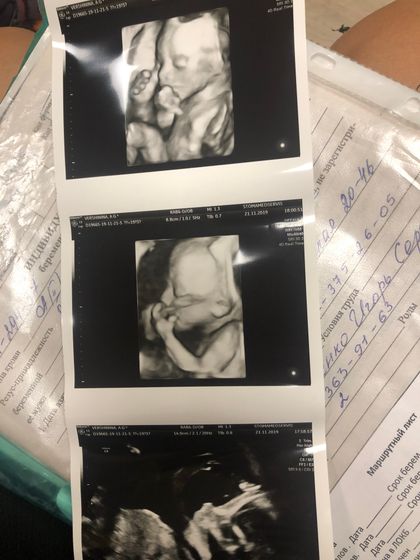

Мы узнали пол ??? Ждём вторую девочку! ??

Муж так ждал сына ? Но видимо потом придётся ещё за третьим идти)))) Взяли на узи дочку старшую, она сама попросилась) И все дружно узнали кто же новый член семьи)) Полинка очень обрадовалась сестричке)) Кстати она все это время очень уверенно говорила мне, что будет девочка! Как будто знала ? Ох теперь думаю над именем. Малявка очень смешная, теребила пуповинку в пузике. Эмоции зашкаливали. Такая уже там большая выросла, малышка моя☺️